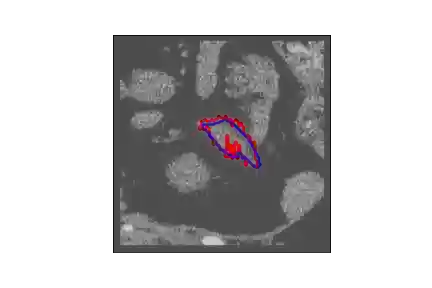

The human annotations are imperfect, especially when produced by junior practitioners. Multi-expert consensus is usually regarded as golden standard, while this annotation protocol is too expensive to implement in many real-world projects. In this study, we propose a method to refine human annotation, named Neural Annotation Refinement (NeAR). It is based on a learnable implicit function, which decodes a latent vector into represented shape. By integrating the appearance as an input of implicit functions, the appearance-aware NeAR fixes the annotation artefacts. Our method is demonstrated on the application of adrenal gland analysis. We first show that the NeAR can repair distorted golden standards on a public adrenal gland segmentation dataset. Besides, we develop a new Adrenal gLand ANalysis (ALAN) dataset with the proposed NeAR, where each case consists of a 3D shape of adrenal gland and its diagnosis label (normal vs. abnormal) assigned by experts. We show that models trained on the shapes repaired by the NeAR can diagnose adrenal glands better than the original ones. The ALAN dataset will be open-source, with 1,594 shapes for adrenal gland diagnosis, which serves as a new benchmark for medical shape analysis. Code and dataset are available at https://github.com/M3DV/NeAR.